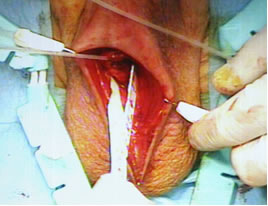

Произведена сборка и заполнение коннекторных трубочек и частей сфинктера физиологическим раствором. На уретру с помощью фиксирующего окна установлена манжетка (4,0см).Пальпаторно определено наружное паховое кольцо справа. Ножницами рассечена поперечная фасция, послеоперационные спайки. Окно расширено пальцем и в паравезикальное пространство справа имплантирован баллон сфинктера.Баллон наполнен 22мл физиологического раствора. Клапан сфинктера имплантирован в мошонку. Соединяющие трубки укорочены таким образом, чтобы они не провисали и не перегибались. Коннекторные трубки герметично соединены посредством замков, которые фиксируются между собой специальным инструментом. Выполнен антибактериальный лаваж. Дренирование раны не выполнялось. Ушивание раны. Асептическая наклейка.

Основные этапы операции.